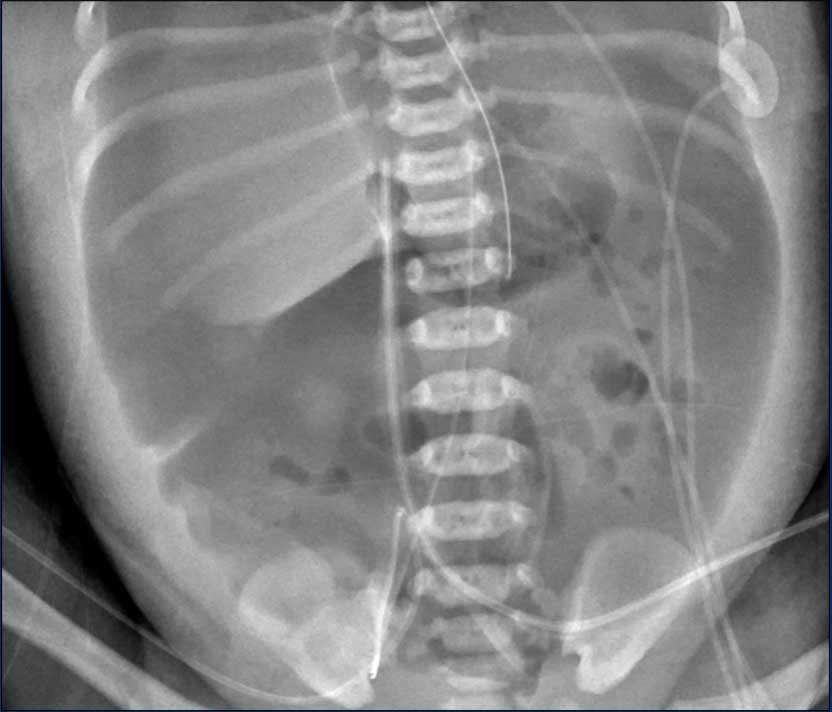

Phân bố hơi trong lòng ruột

Trên X-quang, cần đánh giá phân bố hơi trong lòng ruột.

Giãn ruột

Để đánh giá mức độ giãn, có thể sử dụng chiều rộng liên cuống đốt sống L2 làm mốc tham chiếu.

Phân bố hơi trong ruột

Cần đánh giá sự phân bố hơi trong ruột, vì các vùng thiếu hơi khu trú có thể đại diện cho đoạn ruột bệnh lý.

Do góc phần tư dưới phải là vị trí thường bị tổn thương nhất, đây cũng là vùng thường xuyên nhất có biểu hiện vắng mặt hơi ruột.

Một dấu hiệu quan trọng khác là quai ruột cố định (persistent loop).

Hình ảnh

X-quang bụng cho thấy các quai ruột giãn và phân bố hơi không đều với vùng thiếu hơi ở góc phần tư dưới phải.